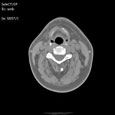

Критический стеноз правой внутренней сонной артерии. Критический стеноз правой внутренней сонной артерии

Пациент U., 69 лет

Критический стеноз правой внутренней сонной артерии.

ЦКБ5 Южной железной дороги, отделение лучевой диагностики.

На КТ-сканах шеи (до уровня основания черепа) в условиях ангиографического режима (в/в ультравист 300 - 100,0 мл 2,5 мл/сек.) определяется окклюзия правой внутренней сонной артерии на 15 мм дистальнее бифуркации общей сонной артерии, дистальнее контрастирование просвета артерии не определяется. Ассиметрично контрастированы яремные вены (справа интенсивность контрастирования значительно ниже).